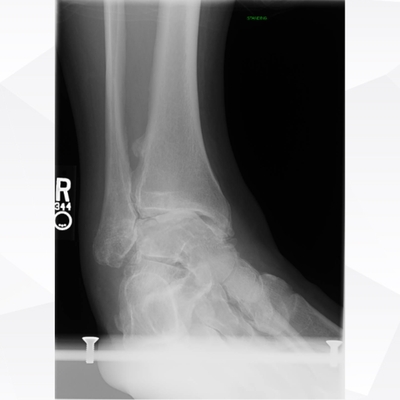

Click on an image below to view more info.